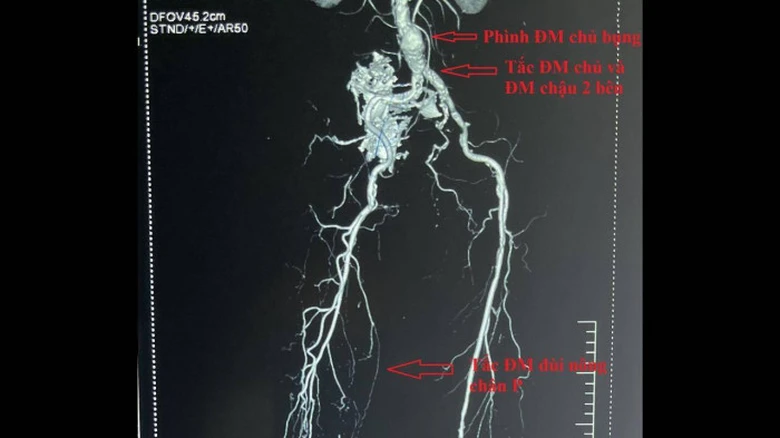

Kết quả chụp cắt lớp vi tính mạch máu có cản quang, siêu âm Doppler mạch máu chi dưới: phình tắc ĐMC chậu, tắc động mạch đùi khoeo bên phải do vôi hóa và huyết khối.

Các bác sĩ đã hội chẩn, chẩn đoán: phình tắc ĐMC chậu hai bên kèm theo tắc đùi nông chân phải. Đây là tổn thương phức tạp, có chỉ định phẫu thuật cắt túi phình ĐMC bụng và bắc cầu ĐMC đùi hai bên bằng ống ghép mạch máu nhân tạo...

Hình ảnh chụp cắt lớp vi tính có cản quang.